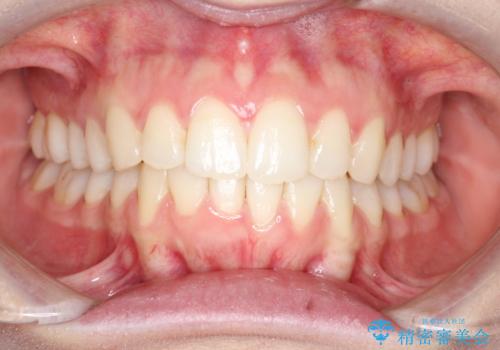

【インビザライン】前歯のガタガタをなおしたい。

- 前歯の凸凹を主訴に来院されました。

インビザラインにて奥歯の遠心移動を行いながら、前歯のガタガタを改善することができました。